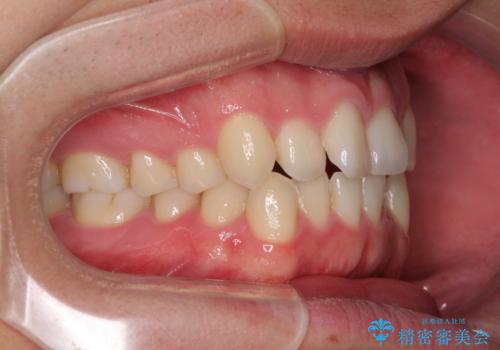

狭い歯列と前歯のデコボコ インビザラインによる矯正治療

- 上下前歯のデコボコを気にして来院された患者様です。

インビザラインによる上下歯列の拡大と、IPR(歯と歯の間を削る)にるスペースの獲得により、前歯のデコボコと狭い歯列を改善することとしました。

比較的軽度な歯列不正であったため、治療期間はそれほど長くはならないと予想されました。

しかしながら、あまりしっかりとマウスピースを装着していなかったため、思いの外期間が長引いてしまいました。

また、仕上がりの歯列にも若干の叢生が残ってしまいました。